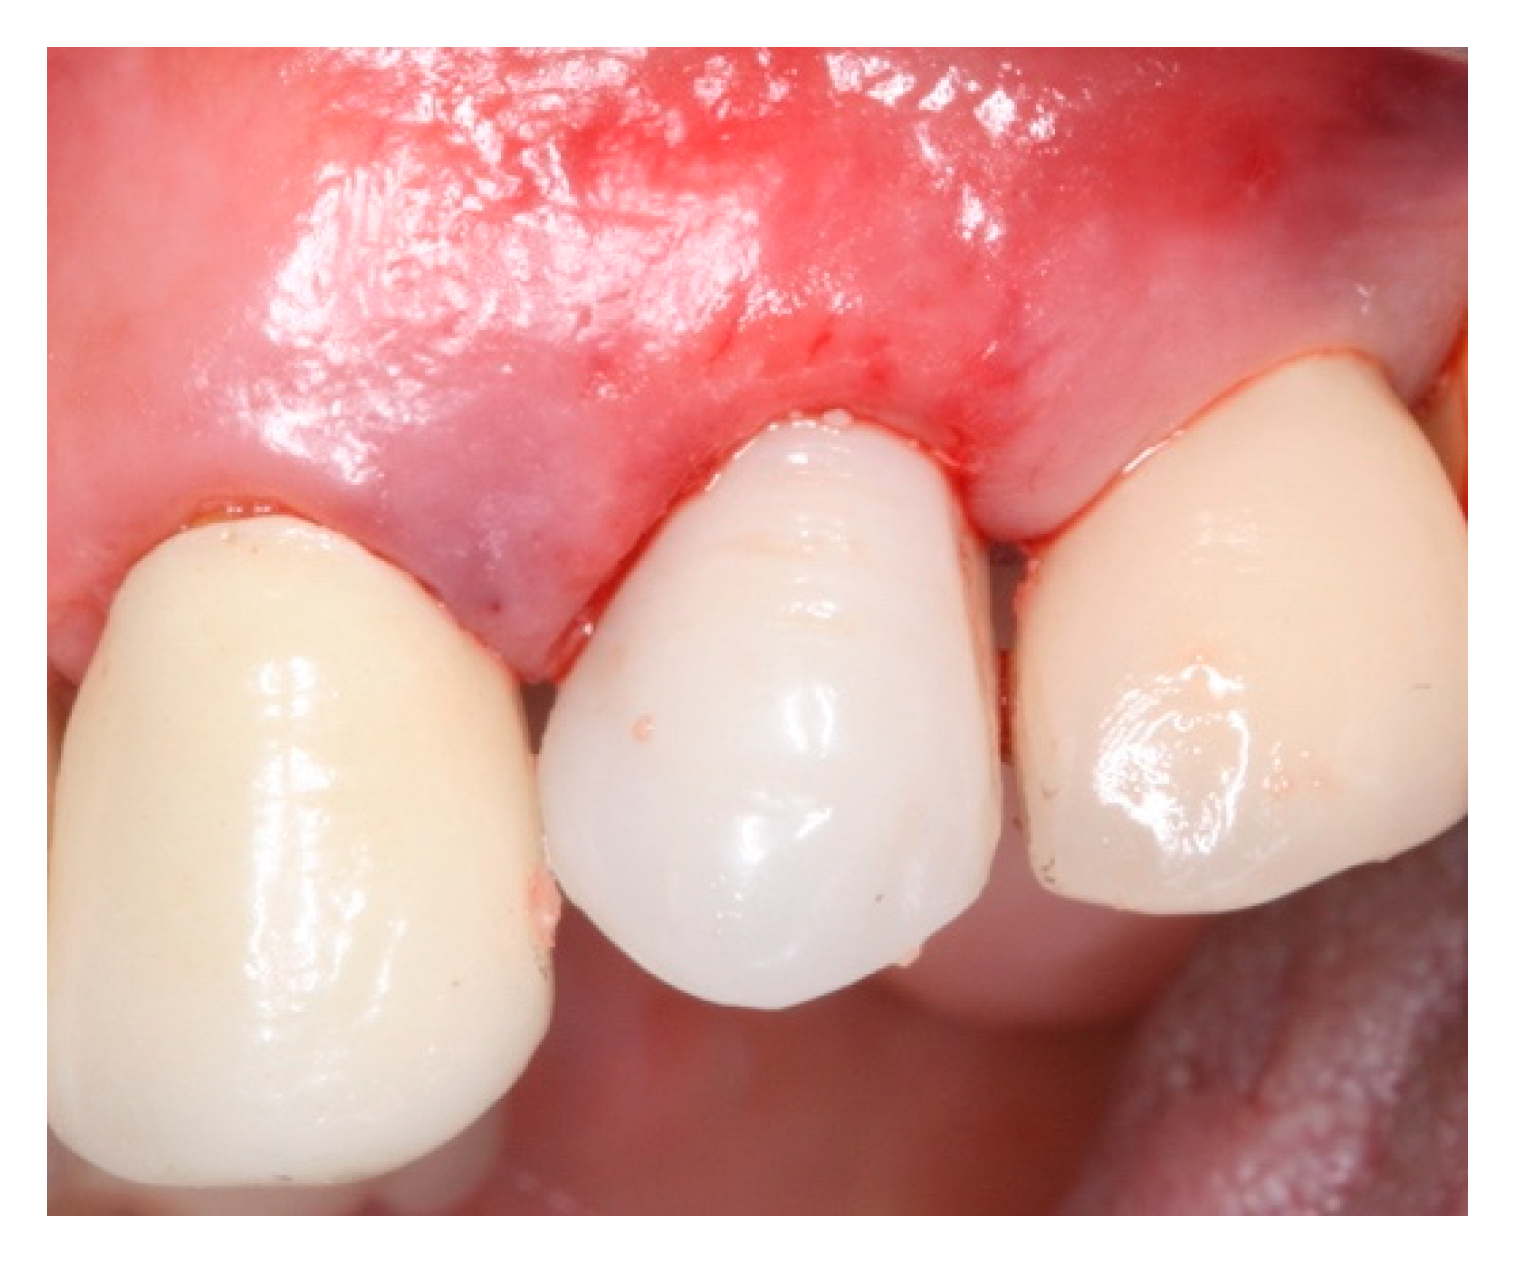

2. Materials and Methods

3. Results